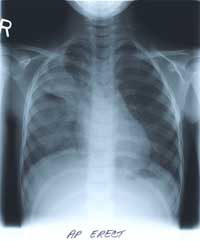

BELOW

is her CHEST X-RAY taken during the hospitalization.

Previous films from her NICU stay are not available.

WHAT ARE YOUR FINDINGS?